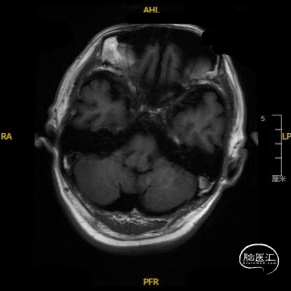

➢ 入院后头核磁检查

患者主因言语不利3天入院,头核磁提示右侧额、顶叶多发低灌注梗塞,脑血管造影提示右侧颈内动脉开口重度狭窄,为责任血管,另外患者前交通动脉、右侧后交通动脉开放不良,并且狭窄严重,考虑到高灌注风险,决定分期处理,一期小球囊扩张改善供血,二期支架成型。